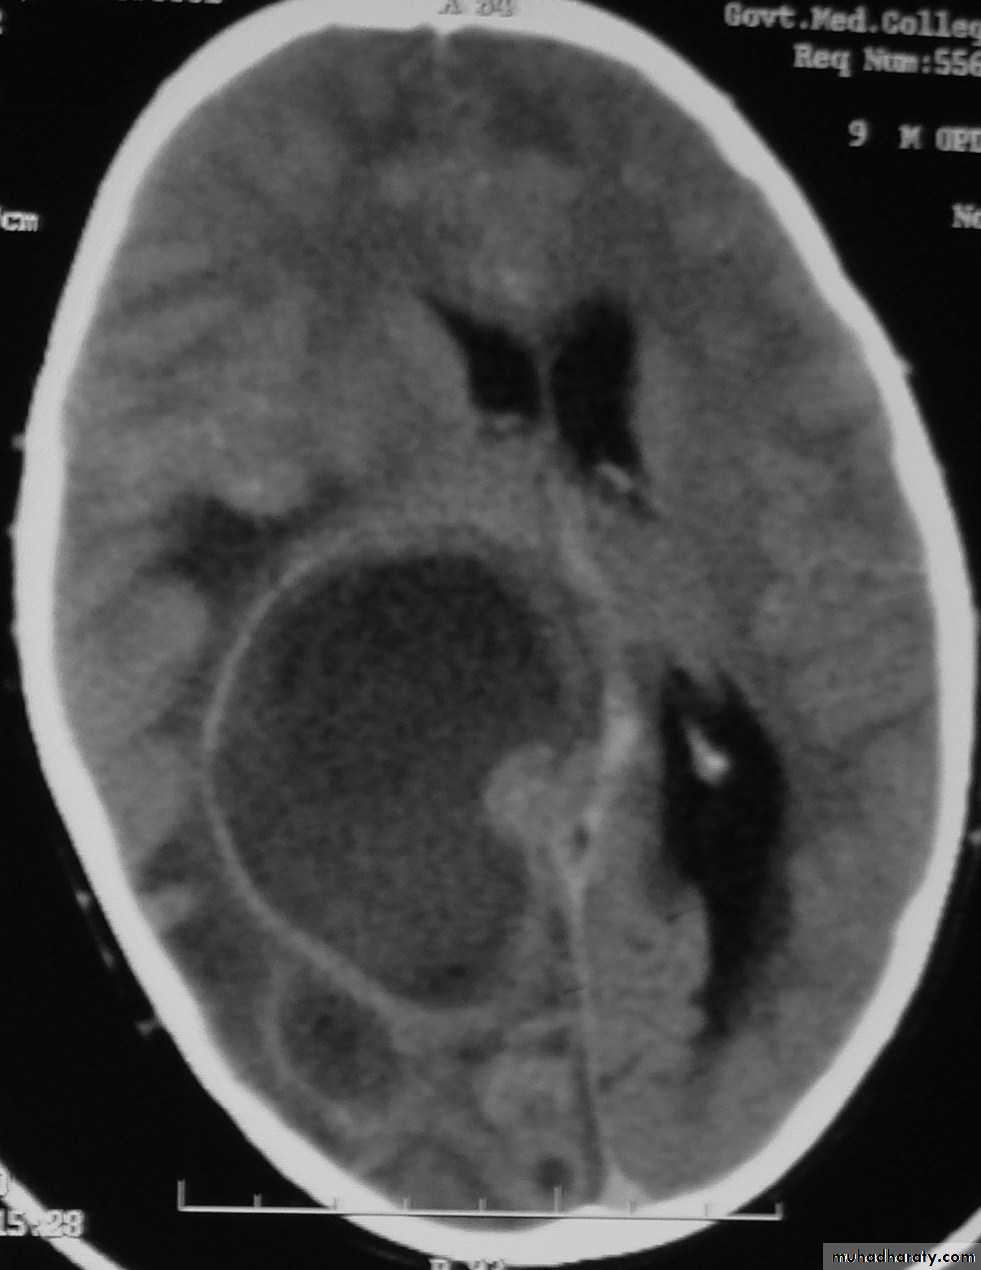

Brain Abscess

• B. Radiological Investigations:

• CT or MRI is the investigation of choice.

• CT Brain is performed with and without contrast.

• MRI is done with gadolinium enhancement.

• They will show a single (or multiple) space occupying lesion that is well delineated with an enhancing wall, with variable surrounding oedema.

Brain Abscess CT without contrast

Neurosurgery

Brain Abscess CT with contrast